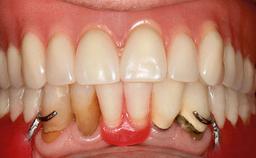

Improving an Existing Implant-supported Denture in an Alzheimer Patient with Bipolar Affective Disorder with Moderate Depression and Dementia

An 83-year-old man presented together with his caregiver at the dental department of the Medical University of Innsbruck, Austria with complaints of swelling in the right maxillary canine area and loss of retention of his 5-years-old mandibular denture. The patient had a significant medical history (20 years) of bipolar affective disorder with moderate depression (F 31.3) and dementia in Alzheimer’s disease (F 00.2). The patient had been in ambulant psychiatric therapy for his depressive illness for the past 20 years. He lived alone and had no children; his sister assisted with daily living. She reported that the patient exhibited compulsive hoarding behavior. In the previous two months, she had noted increasing disorientation and vertigo in the patient. She therefore accompanied him for a medical consultation at the Department of Psychiatry and Psychotherapy of the Medical University of Innsbruck. He was released home after a 6-week inpatient stay.

Case Type Edentulous Mandible

Jaw Mandible

Area Full-Arch